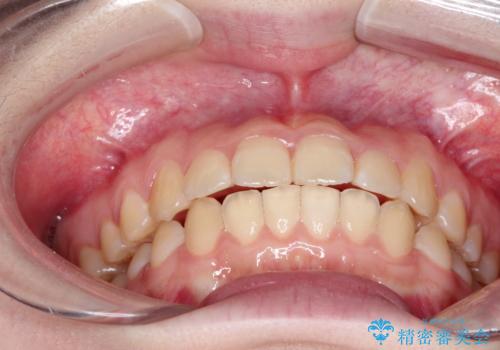

受験生ということもあり、来院頻度が少ないマウスピース矯正で治療が終了できたことに満足いただけました。

上下の正中が一致していませんが、受験を控えているためご本人の希望もあり、いったん終了とさせていただきました。

治療の中断・再開が容易なのもインビザライン治療のメリットといえます。